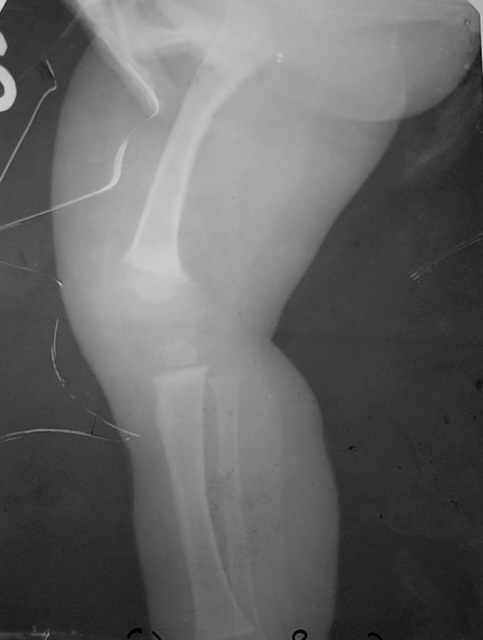

Мальчик, 5 лет. Гипохондроплазия. Генетическая предрасположенность к нарушению физического развития. Ребенок от I беременности, протекавшей нормально. ТОРЧ-негативный. Неврологических расстройств нет. Семейный анамнез: средний рост мужчин в семье 150 см, антропологические особенности - короткие конечности, длинное туловище, крупный череп. Вес 15 кг, рост 92 см.Тактика лечения? Заранее благодарю! С уважением,А.В.Владзимирский